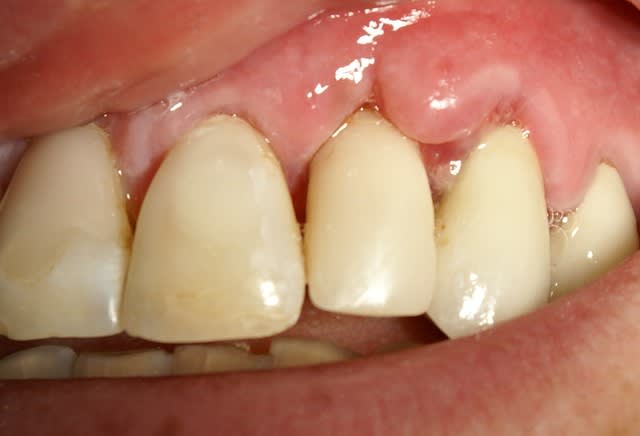

Tout à fait d'accord growler et c'est d'ailleurs ce que l'on peut voir sur le cas suivant. Fracture radiculaire, aucune infection periradicualire. Extraction et implantation immediate. Espace existant entre l'implant et l'alvéole est comblé par du BioOss. Un logement sous gingival est formé en vestibulaire et palatin de facon à pouvoir recouvrir le tout par BioGide et un conjonctif enfoui.

L'implant est de 15mm mais l'alvéole était large et 50% environ de la surface implantaire n'était en contact qu'avec du BioOss. J'ai pour cela préféré enfouir.

Situation semblable.

Jeune homme, 20 ans, accident de vélo.

Perte de 11 et 21.

Arrive dans mon cabinet 8 jours post trauma.

J'ai placer sous antibio et 2 jours après j'ai curetté les alvéoles, fait lambeau (perte de paroie buccale), placer 2 4,6 X 15 mm en palatin, greffe MINEROS, membranne (suturée sous le lambeau palatin + 2 tacs en titane au buccal).

Extension du lambeau au buccal et fermeture.

Ah oui, freinectomie laser en mêm temps, histoire de s'occuper un peu. Pas de temporisation sur implants avec une perte d'os au buccal. Prothèse acrylique amovible de transition, placée 7 jours post-op.

La 2e photo est 7 jours post-op, la sem dernière.

Zéro enflure, zéro douleur, pas d'anelgésique.